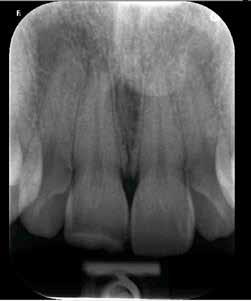

A klinikai vizsgálat során az UR1 reagál a viabilitási tesztre, és az ugyanazon a napon készült röntgenfelvételen nem mutat periapikális elváltozásokat (1. ábra).

1. ábra: Röntgenfelvétel periapikális elváltozás nélkül. – 2. ábra: Az UR1 elszíneződése és palatális helyzete.